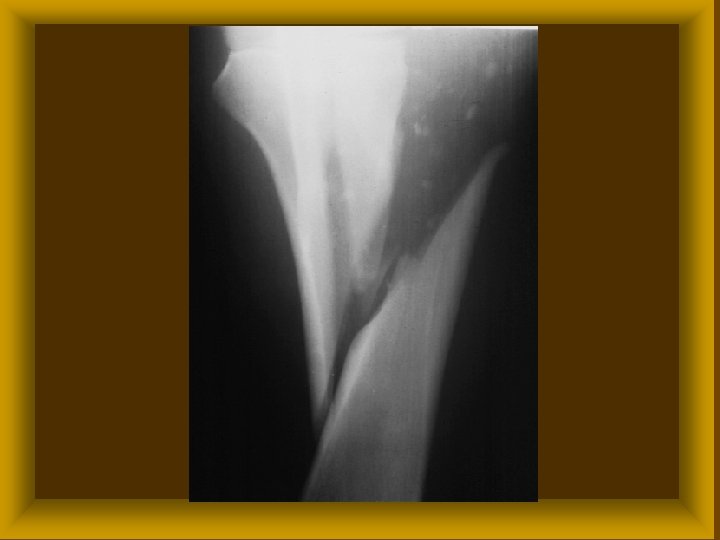

FRACTURÁK MORPHOLÓGIÁJA II Törési sík alapján : * haránt * hosszirányú * ferde * spirális Ø Törési darabok alapján * egyszerű * többszörös * rom törés Ø

FRACTURÁK MORPHOLÓGIÁJA III Ø Fractura sine dislocatione Ø Fractura cum dislocatione * ad longitudinem * ad latus * ad axim * ad periferiam